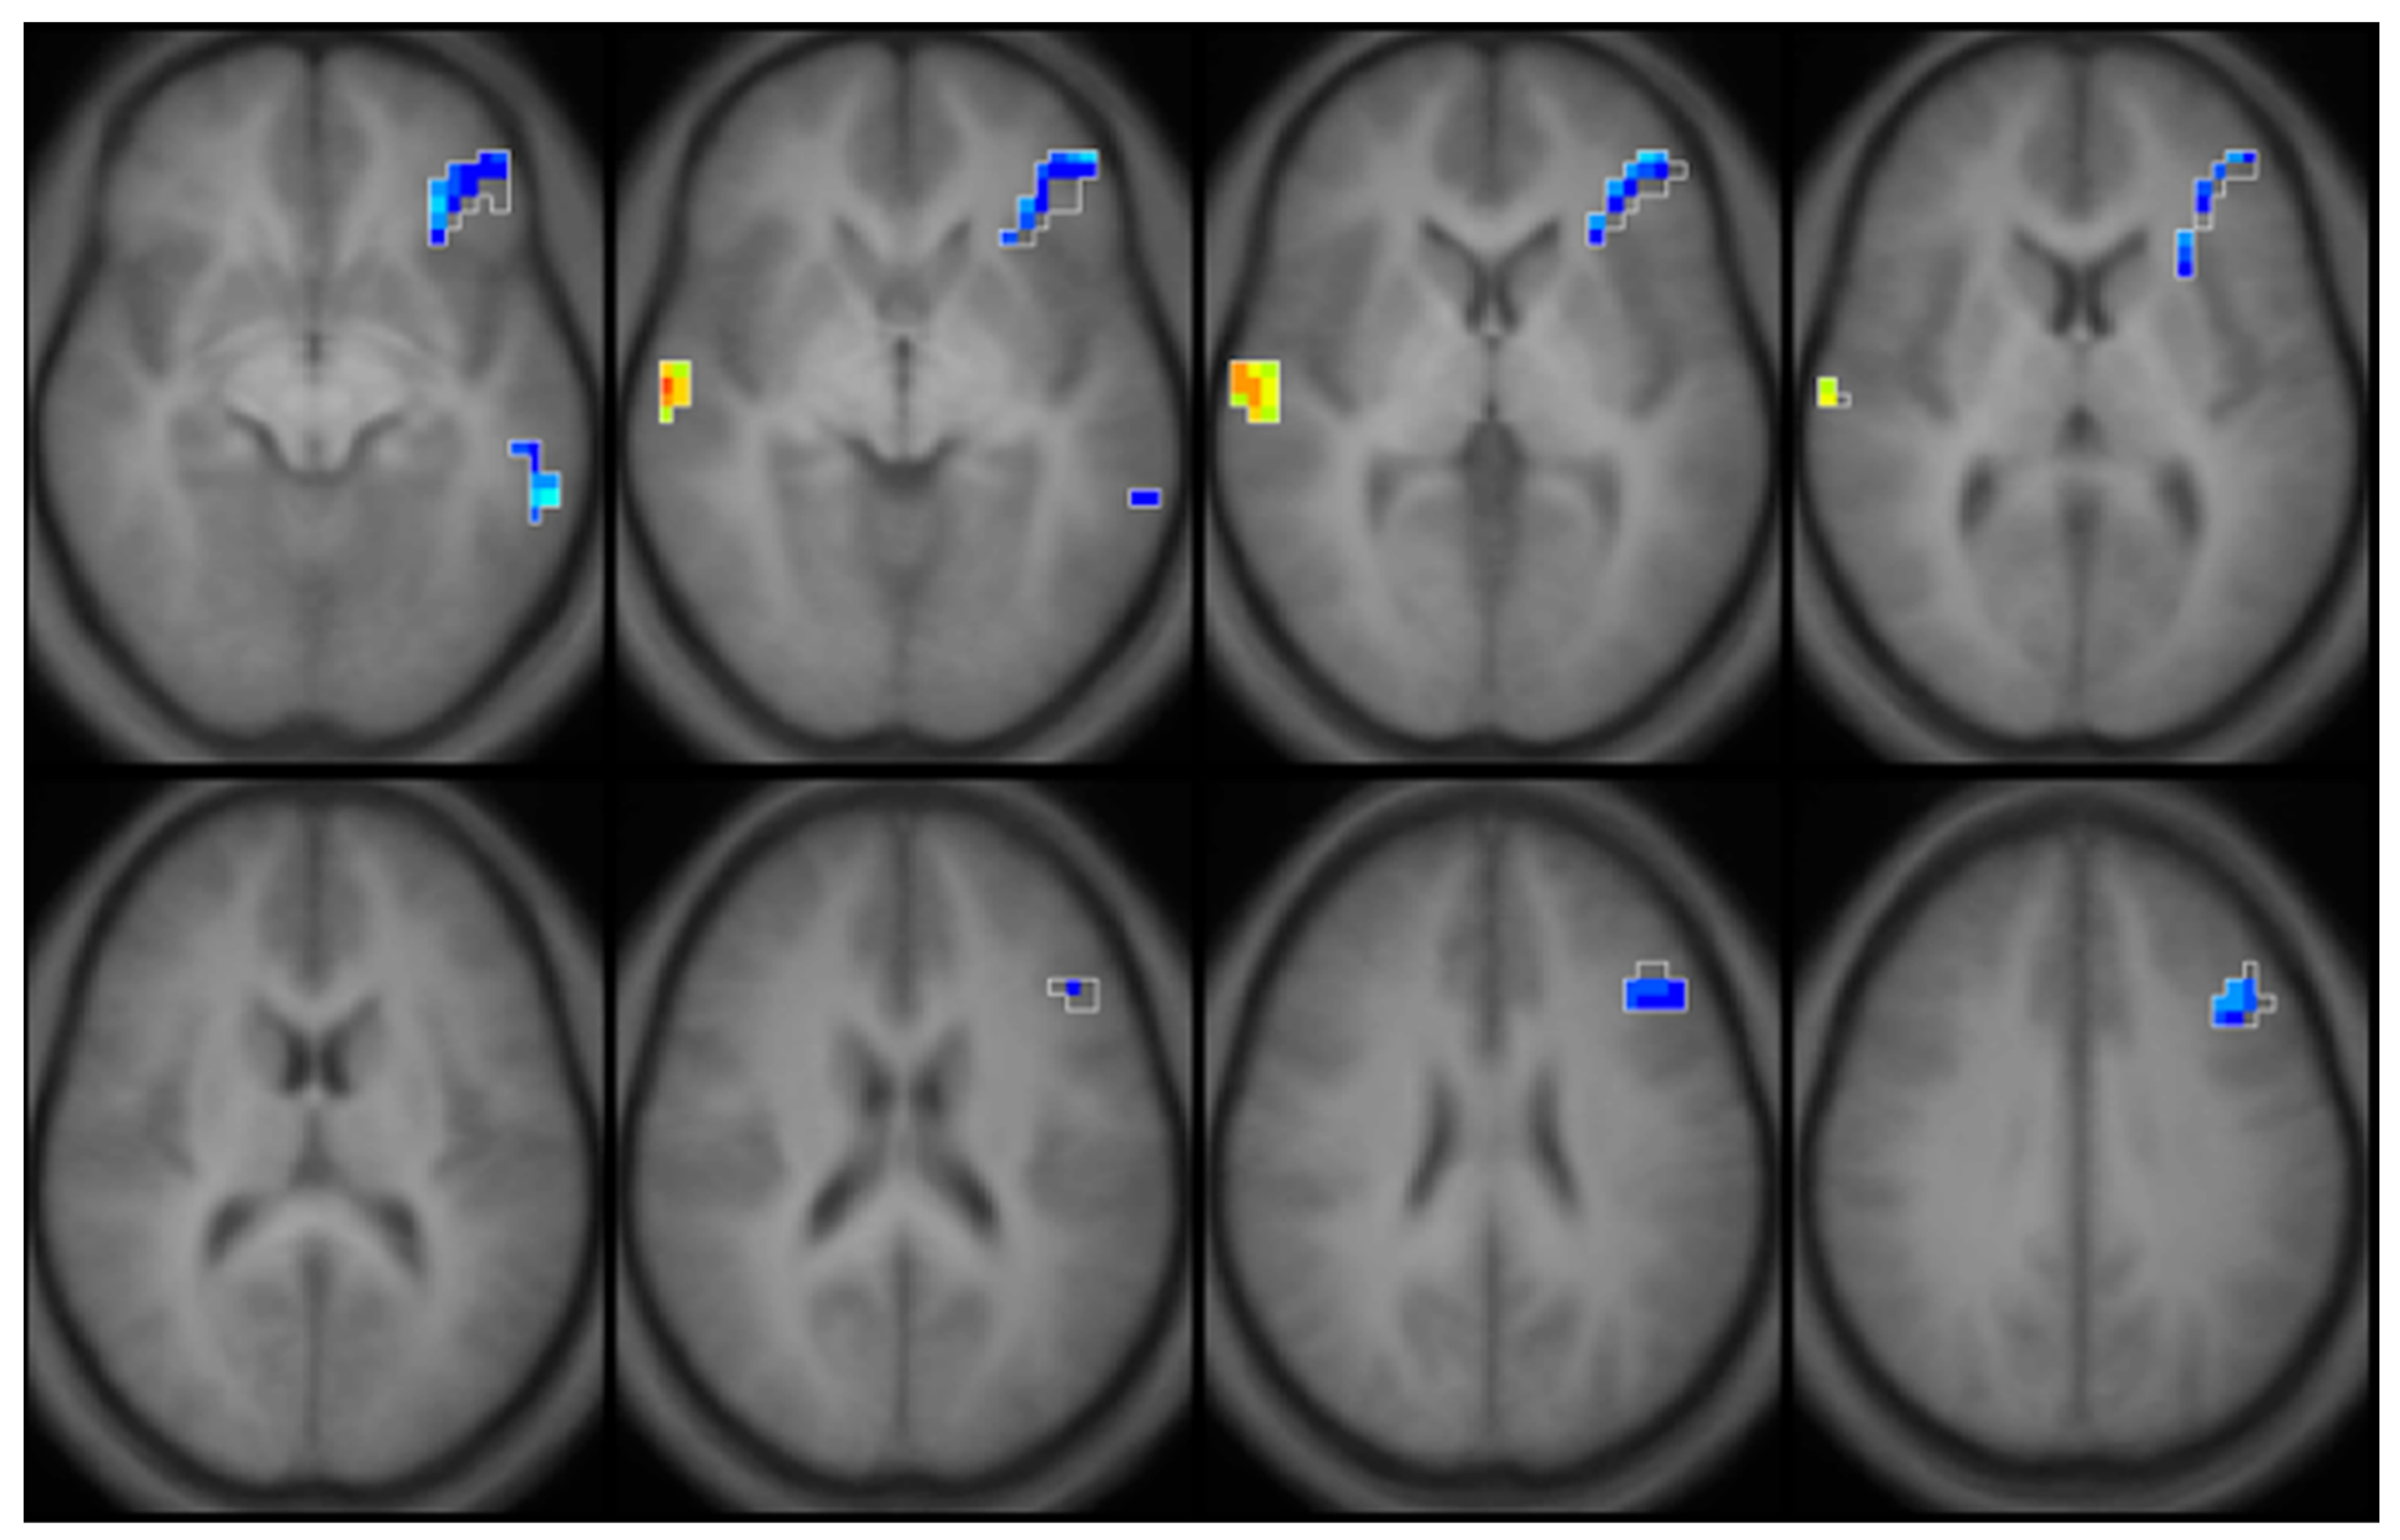

- Lao, Y.; Dion, L.A.; Gilbert, G.; Bouchard, M.F.; Rocha, G.; Wang, Y.; Lepore, N.; Saint-Amour, D. Mapping the basal ganglia alterations in children chronically exposed to manganese. Sci. Rep. 2017, 7, 41804. [Google Scholar] [CrossRef] [Green Version]

- Dion, L.A.; Bouchard, M.F.; Sauve, S.; Barbeau, B.; Tucholka, A.; Major, P.; Gilbert, G.; Mergler, D.; Saint-Amour, D. MRI pallidal signal in children exposed to manganese in drinking water. Neurotoxicology 2016, 53, 124–131. [Google Scholar] [CrossRef]